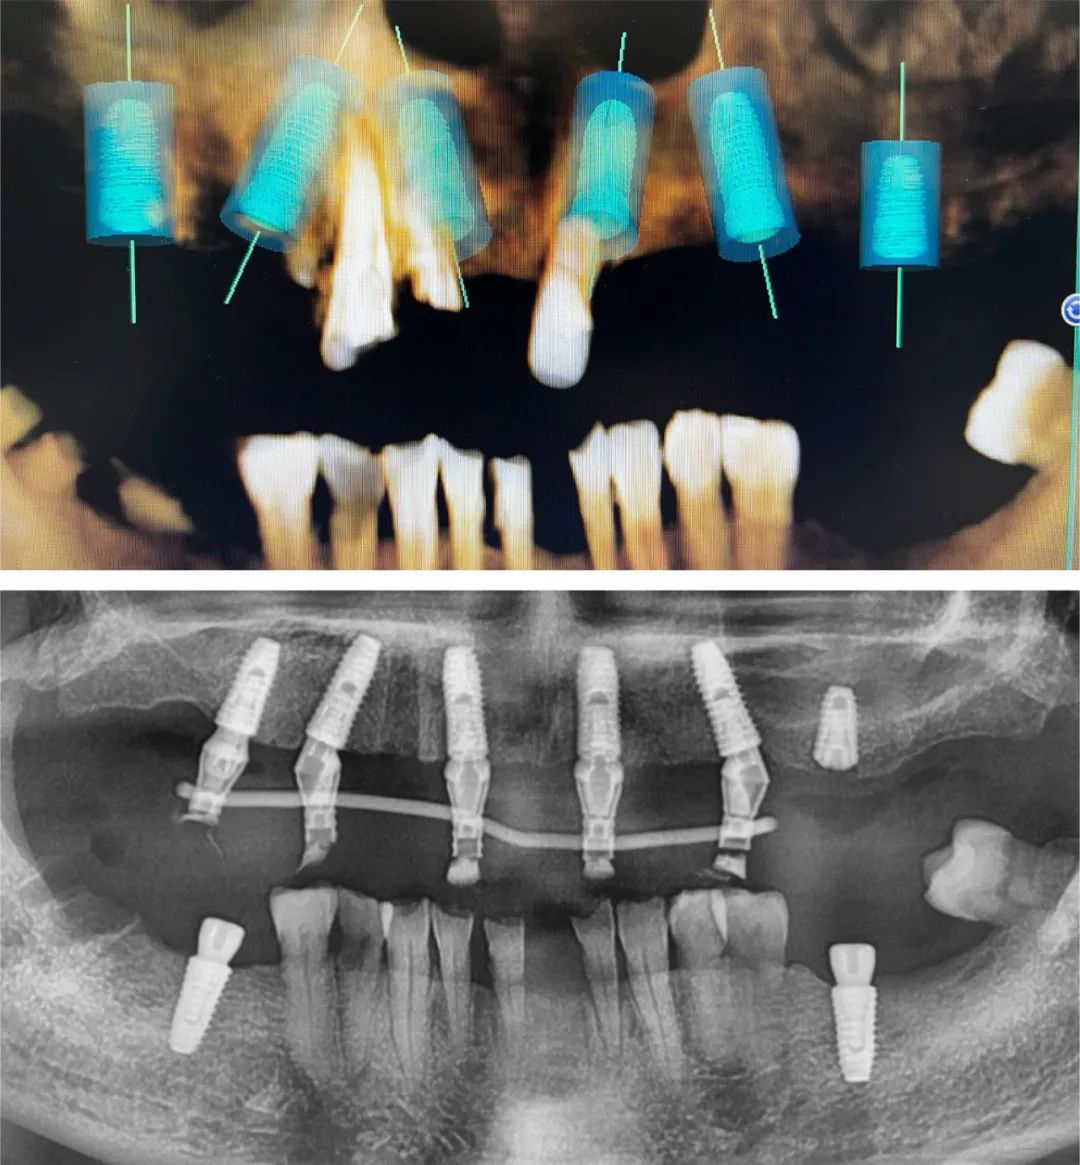

2017年,张嘉宇开始尝试数字化种植。彼时,口腔种植技术已在国内逐步普及,但数字化对于大多数种植医生来说还是一个陌生的领域。

“数字化种植包括数字化口腔扫描、数字化种植方案设计和数字化导板导航手术等几个环节,它比传统的人工取模更精准、更舒适,手术不需要翻瓣,创伤小,是对现有种植技术的一个有益的补充。”

基于对常规种植和数字化种植的丰富临床经验,张嘉宇认为后者当然有其相应的优势,但任何技术都只是达成治疗目标的一个工具。工欲善其事,必先利其器,但不要为器所累,数字化种植和传统种植殊途同归,各有优势,需要合理选择。

“单颗或几颗牙齿缺失时,口腔里还有足够多的牙来固定导板,采用数字化导板导航进行种植还是比较精准的,但如果缺的牙比较多,导板的固定只能采用牙和口腔黏膜的混合支持式,因为牙和黏膜的强度、弹性是不一样的,可能会影响到导板的稳定性,从而影响种植的精准度。另外,导板的硬度也会影响到种植效果。”

张嘉宇认为,复杂的种植病例和需要种植位置极度精确的,差误不能超过0.5毫米的病例,数字化导板导航种植是一个不错的选择。

2019年来成都后,从一开始的单颗种植到常规的多颗种植,从简单植骨到内提升、外提升到半口全口种植,张嘉宇不断解锁新技能,持续稳步向前。随着案例量的累积,2021年以后,他的技术突飞猛进,慕名而来的患者越来越多,他也越来越忙,但仍保持着术前预备的习惯。

“我每一台手术之前都要分析到位,不打无准备之仗。因为之前机构的手术室没有显示屏,手术时看不到患者的CBCT,只能凭着记忆和肉眼观察去做,对于难度较大的案例,我都会在术前把模拟植入的位置摆好,存在手机里反复熟悉,做到心中有数。”